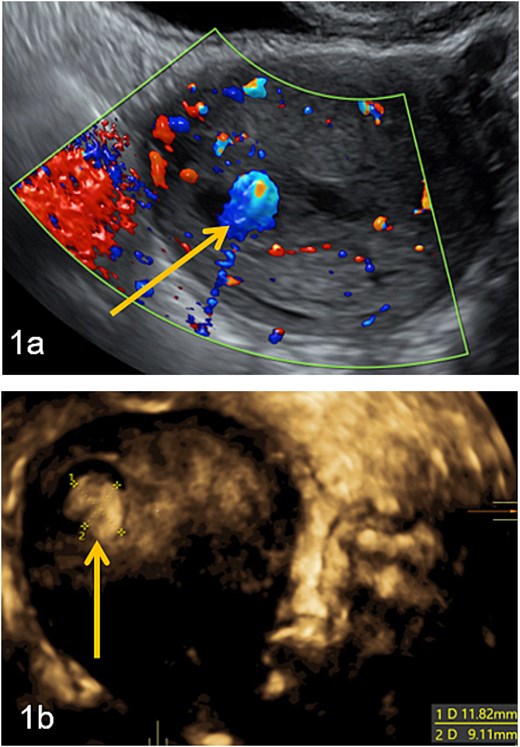

Doppler and 3D-pelvic ultrasound revealed a 12 × 9 mm vascularized intrauterine mass with a Doppler color score of 4, with no signs of myometrial invasion (Fig. 1). Two treatment options were proposed to the patient: initiation of single agent chemotherapy with methotrexate or surgical removal of the retained uterine tissue using a mechanical hysteroscopic tissue removal system.

Intra-uterine vascularized mass (arrows) diagnosed by Doppler (a) and 3D-pelvic (b) ultrasound. The Doppler color score is 4 and there is no suspicion of myometrial invasion (continuous halo surrounding the lesion).